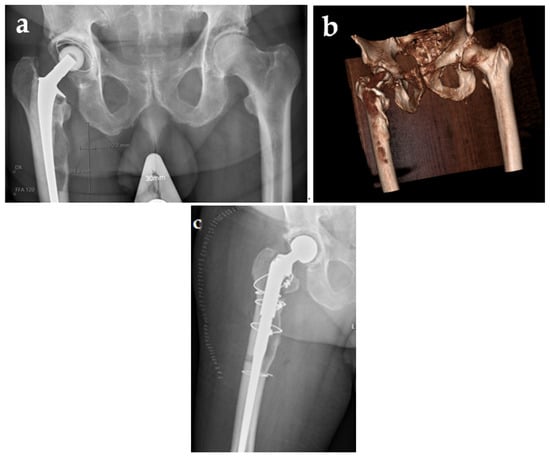

A 75-year-old still-active male farmer with a history of atrial fibrillation and diabetes mellitus underwent a cemented right-sided total hip arthroplasty (Lubinus) due to coxarthrosis in 2006. In April 2018, the patient consulted his primary care physician due to arthralgia of the contralateral hip and suspicion of coxarthrosis. An X-ray was performed and en passant an osteolytic process, 2 × 9.5 cm, with a very thin corticalis of the right hip, was noted (Figure 1a).

Figure 1.

Preoperative X-ray (a), CT scan (b), and postoperative X-ray of one-stage revision arthroplasty (c).

The patient was referred to the Department of Orthopedic Surgery at Örebro University Hospital, Sweden, where further investigation by CT scan verified the thin corticalis and revealed a suspected breakthrough (Figure 1b). Ultrasound-guided biopsies of the osteolytic process were performed, and showed growth of Staphylococcus hominis in 1/5 samples, Staphylococcus warneri in 1/5, and Corynebacterium spp. in 1/5. The latter isolate was stored and subsequently in this study typed as Corynebacterium minutissimum.

Due to the obvious risk of a periprosthetic fracture, a one-stage revision arthroplasty surgery was performed in September 2020. Both the cup and the femoral stem were exchanged. An osteotomy was implemented in order to excise all the cement, but the thin corticalis was also fractured medially. Both the osteotomy and the fracture were repositioned and fixed by cerclage. Five perioperative tissue biopsies and synovial fluid did not show any growth. However, delayed wound healing and prolonged secretion were noted, and a CT scan 9 days postoperatively revealed encapsulated liquid not communicating with the joint, assumed to be a seroma or hematoma. The patient was discharged on day 11, but readmitted two days and again three days later due to wound leakage. This leakage was assessed as drainage of seroma or hematoma, since the patient was afebrile. It is possible that the leakage diminished temporarily, but on a scheduled early follow-up visit three weeks after surgery, profuse leakage of serous fluid and a phlegmonous process surrounding the surgical wound of the hip was noted (Figure 2).